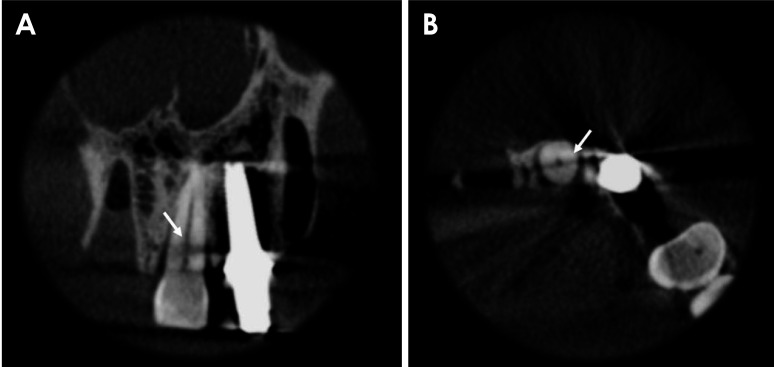

目的:本研究探讨了减少金属伪影(MAR)、应用锐化滤波器及其组合对锥形束计算机断层扫描(CBCT)检查中氧化锆种植体邻近牙齿水平根折(HRF)诊断的影响:将 19 颗单根牙齿(9 颗有 HRF,10 颗没有 HRF)分别置于干燥人类上颌骨的右中切牙牙槽窝中。每颗牙齿旁边都植入了一颗氧化锆种植体。成像使用 OP300 Maxio CBCT(Instrumentarium,芬兰图苏拉)设备进行,设置如下:8 mA 电流、两种 MAR 模式(启用和禁用)、5×5 cm 视场、0.085 mm 像素大小和 90 kVp 峰值电压。四名口腔颌面部放射科医生在两种 MAR 条件下和 3 种锐化滤镜应用水平(无、锐化 1× 和锐化 2×)下独立评估 CBCT 扫描。诊断指标通过双向方差分析(α=5%)进行计算和比较。加权卡帕检验用于评估 HRF 诊断中检查者内部和检查者之间的可靠性:结果:MAR工具的激活、锐化滤波器的使用及其组合对HRF诊断的接收者工作特征曲线下面积、灵敏度或特异性没有显著影响(P>0.05)。检查者内部和检查者之间的一致性从一般到相当可观不等:结论:氧化锆种植体邻近牙齿的 HRF 诊断不受 MAR 激活、锐化过滤器应用或这些工具组合的影响。

Materials and methods: Nineteen single-rooted teeth (9 with HRF and 10 without) were individually positioned in the right central incisor socket of a dry human maxilla. A zirconia implant was placed adjacent to each tooth. Imaging was performed using an OP300 Maxio CBCT (Instrumentarium, Tuusula, Finland) unit with the following settings: a current of 8 mA, both MAR modes (enabled and disabled), a 5×5 cm field of view, a voxel size of 0.085 mm, and a peak kilovoltage of 90 kVp. Four oral and maxillofacial radiologists independently evaluated the CBCT scans under both MAR conditions and across 3 levels of sharpening filter application (none, Sharpen 1×, and Sharpen 2×). Diagnostic metrics were calculated and compared using 2-way analysis of variance (α=5%). The weighted kappa test was used to assess intra- and inter-examiner reliability in the diagnosis of HRF.